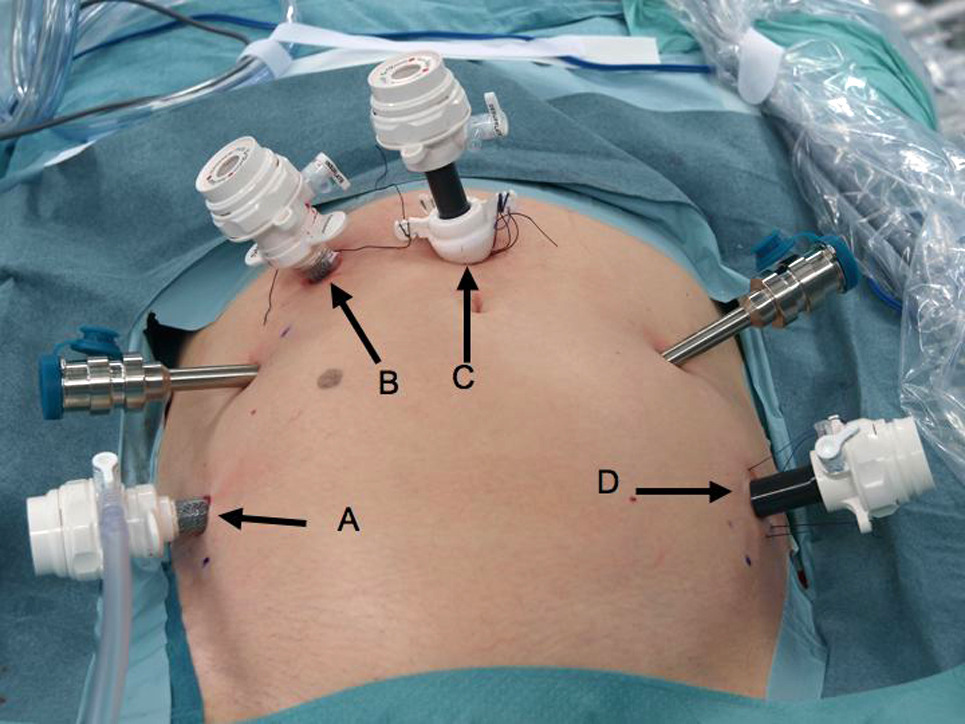

Ameliyat, robotik cerrahi sistemi kullanılarak gerçekleştirilir. Hasta genel anestezi altına alınır ve karın bölgesine birkaç küçük kesi açılır. Robotik kollar bu kesilerden içeri yerleştirilerek cerrah tarafından kontrol edilir. İlk olarak, mesane ve çevresindeki lenf nodları çıkarılır. Erkek hastalarda prostat ve meni keseleri, kadın hastalarda ise rahim, yumurtalıklar ve vajinanın bir kısmı da çıkarılabilir. Sonrasında idrarın vücut dışına atılması için yeni bir idrar yolu oluşturulur.